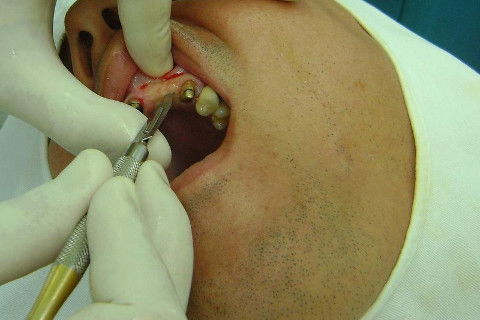

Cirurgia realizada hoje de manhã...No planejamento percebi medindo espessura do rebordo com especímetro que as medidas não estavam muito boas, ou o ideal, em torno de 4,5 a 5 mm ate´o terço médio do rebordo e melhorava no final, com 6 a 7 mm. Optei então por uma pequena expansão usando os expansores rosqueáveis. Aconteceu uma pequena fenestração na hora da fixação dos implantes, especialmente na região do 22 que fraturou o início da tábua óssea, mas não me preocupei porque não foi mais do que 2 mm de fratura em direção apical, o implante ficou infraósseo e com boa estabilidade (60 N no 21 e 40 N no 22). Esta fratura tb não deixou osso completamente solto, foi do tipo galho verde, deixei em posição e suturei normalmente. Só não fiz e nem estava planejado carga imediata mesmo, mais pelo motivo da oclusão inadequada do caso.

Fotos do caso